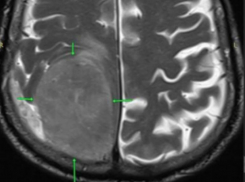

Здоровье В голове 85-летнего пенсионера в Пятигорске обнаружили опухоль размером с лимон

Пациент жаловался на то, что левая часть тела перестала слушаться